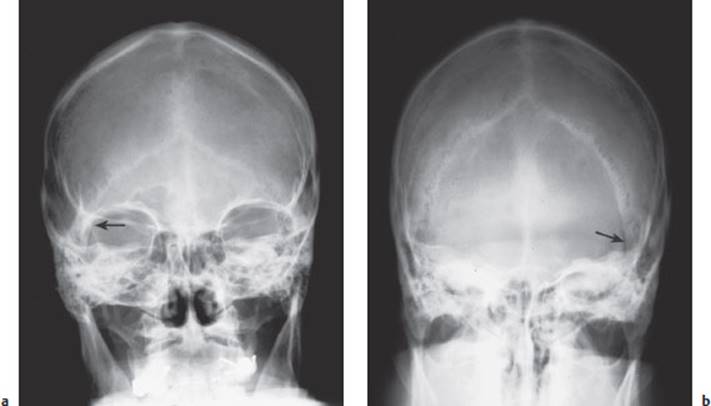

Fig. 4.1 Skull fracture seen in a plain skull radiograph. The a–p (a) and p–a (b) images both reveal a fracture line medial to the lambdoid suture on the right (arrow).